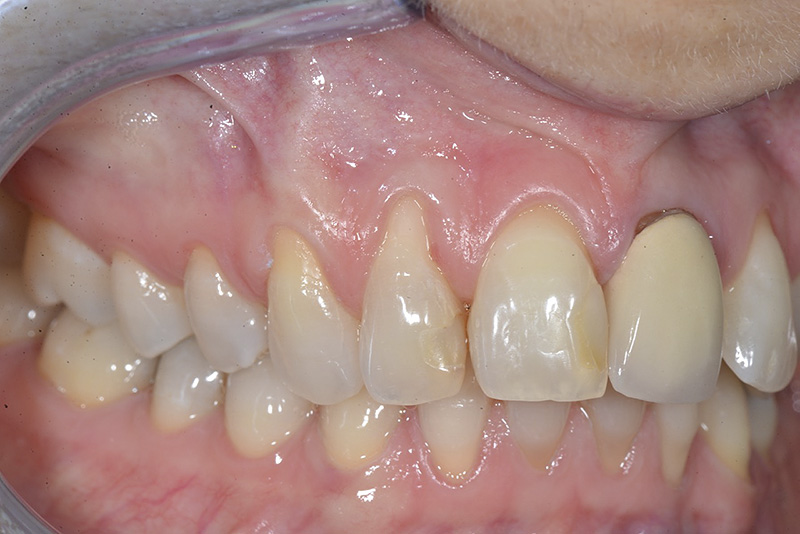

PREMESSA: in seguito all’estrazione dell’incisivo laterale superiore di destra, resasi necessaria per cause batteriche, si decide di affrontare il caso con il posizionamento di un impianto in sostituzione dell’elemento mancante dopo guarigione del sito infetto. Con tecniche rigenerative sia dei tessuti ossei mancanti a causa dell’infezione pregressa, sia dei tessuti gengivali che appaiono inizialmente troppo spostati in alto, si ripristina una corretta morfologia delle parabole (contorni) gengivali e delle papille interdentali (triangoli di gengiva tra due denti vicini).